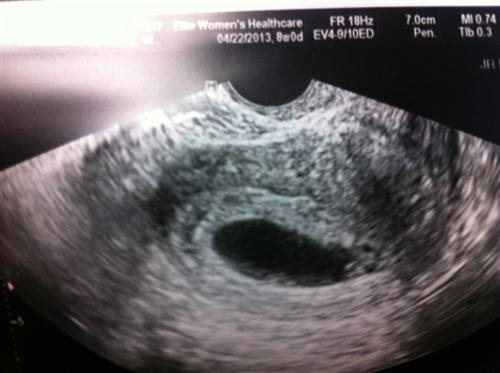

1st sono pic